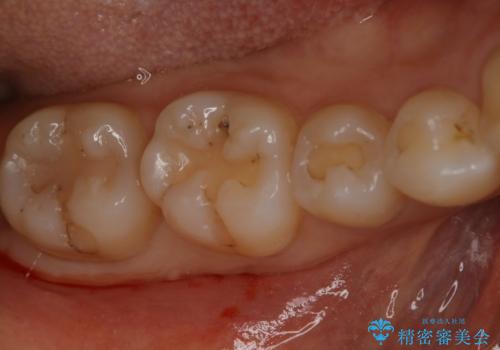

奥歯を綺麗にしたい

- 右下6・7番の咬合面に詰められた保険材料が劣化していたので、審美性・切削量を考慮しセラミックインレー治療を選択しました。

劣化した保険材料・虫歯を全て除去した上で形成しています。